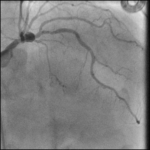

A 71-year-old man presented with new onset CCC class III angina and found to have positive exercise EKG stress test with significant ST-segment depression in multiple leads. PMH: HTN, Ex-smoker…